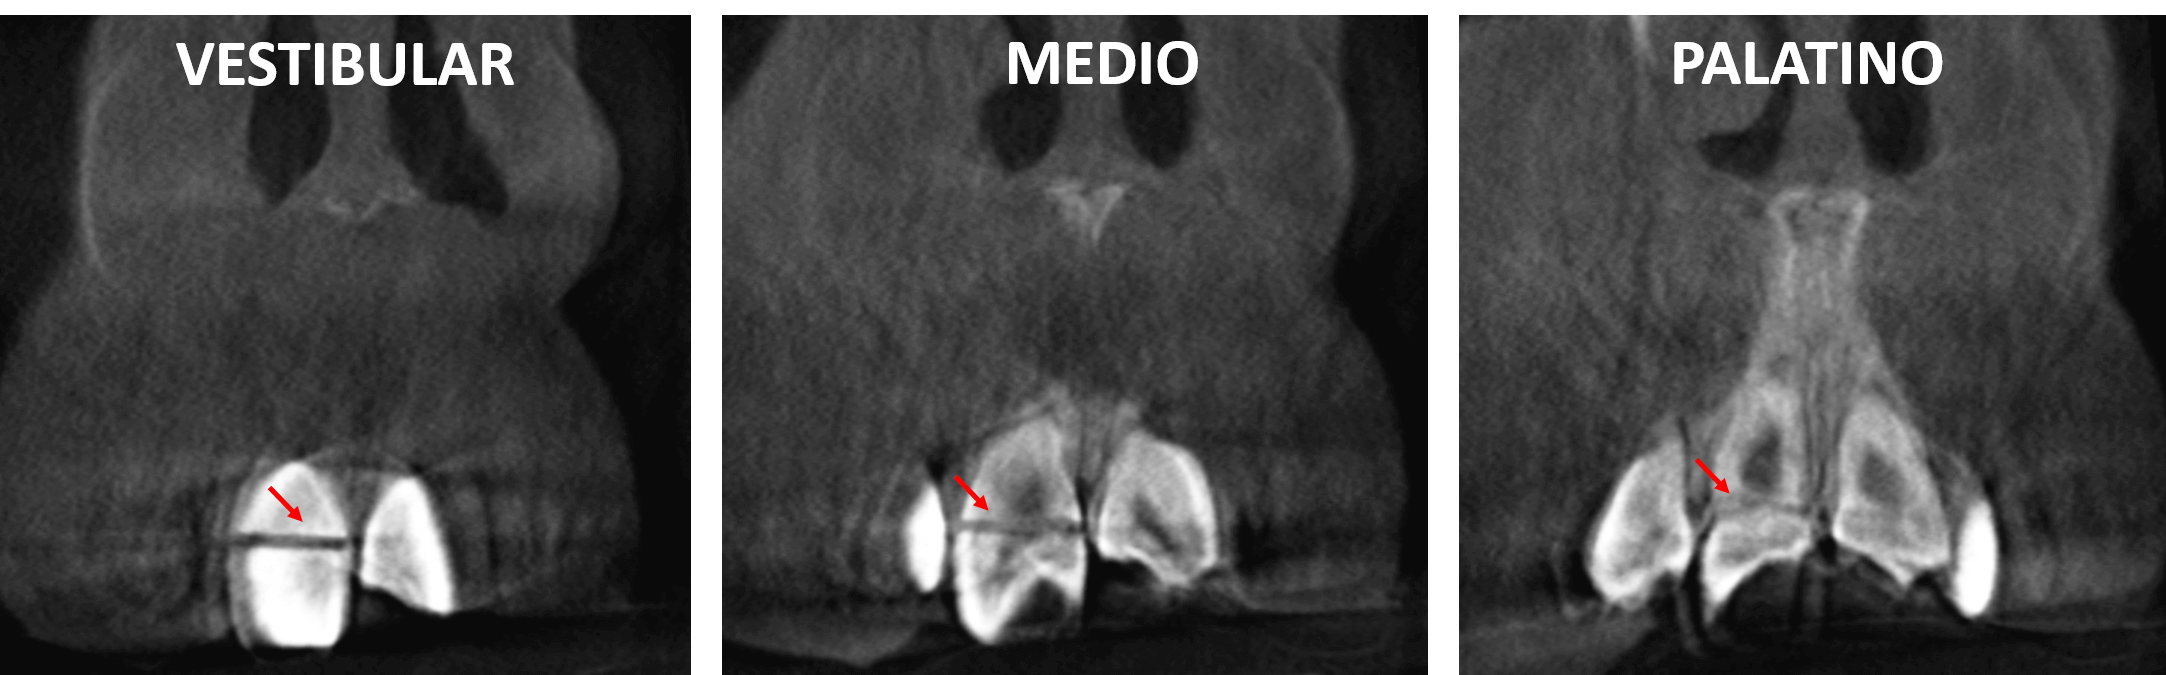

Fig.3

En cortes coronales (Fig.3) se observa nuevamente la disposición mesiodistal de la fractura a nivel del tercio medio coronario por vestibular, el compromiso de la pulpa dentaria en el corte medio y el compromiso de la porción cervical colindante con la raíz.